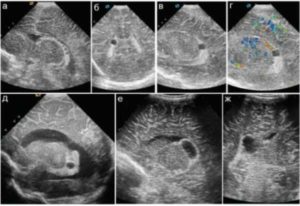

В период эмбриогенеза у плода формируются мозговые пузыри, которые содержат в себе кровеносную сеть. Переплетенные между собой сосуды вырабатывают ликвор. Активная ликворопродукция (секреция) приводит к скоплению жидкости между сосудами и не считается патологическим образованием.

Ультразвук это визуализирует как темное пятно в желудочках мозга, от которого не отражается пучок волны (анэхогенное включение). Точные причины возникновения кист не известны, так как нет достаточных гистологических исследований.

Мнения в медицинском сообществе разошлись и некоторые ученые считают, что кисты, сосудистых сплетений в период эмбрионального развития это одна из стадий формирования мозга. Другая часть врачей склоняется к мнению, что анэхогенное включение в мозге указывает на признак хромосомных аномалий у плода.

Эхографическое ультразвуковое исследование показывает, что киста в головном мозге у плода на сроке 20 недель обычно представляет собой округлое (анэхогенное) образование, обладающее четкими контурами.

Чаще локализуется в системе боковых желудочков. Кисты в зоне сосудистых сплетений в боковых желудочках, расположенных в головном мозге у плода, бывают справа и слева, односторонними и двухсторонними, единичными и множественными.

Размеры существенно варьируются в пределах 1-15 мм в диаметре.